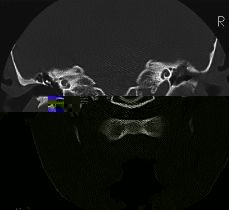

NEURORRADIOLOGÍA Utilidad y limitaciones de la TC en la patología inflamatoria del oído medio

Utility and limitations of CT in otitis media